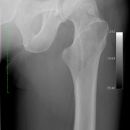

Cam FAI mit herniation pit